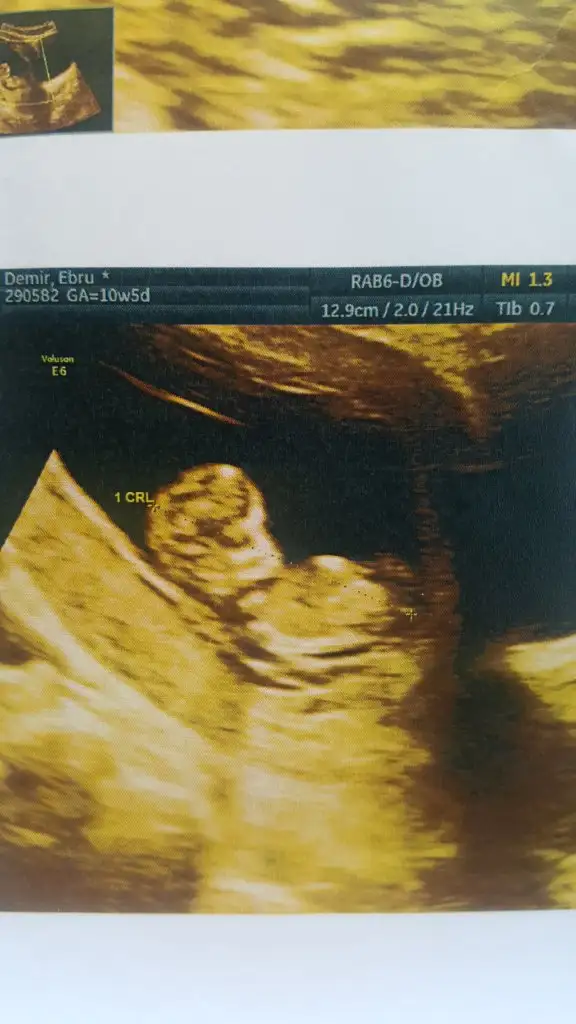

Kizlaar doktordan ciktim cok sukur hersey yolunda 10+5 olduk normalde bugun ultrasonda 11+1 cikti su 1 ay cok stres yaptim cok belirtim falan da olmayinca, cok sukur rahatladim